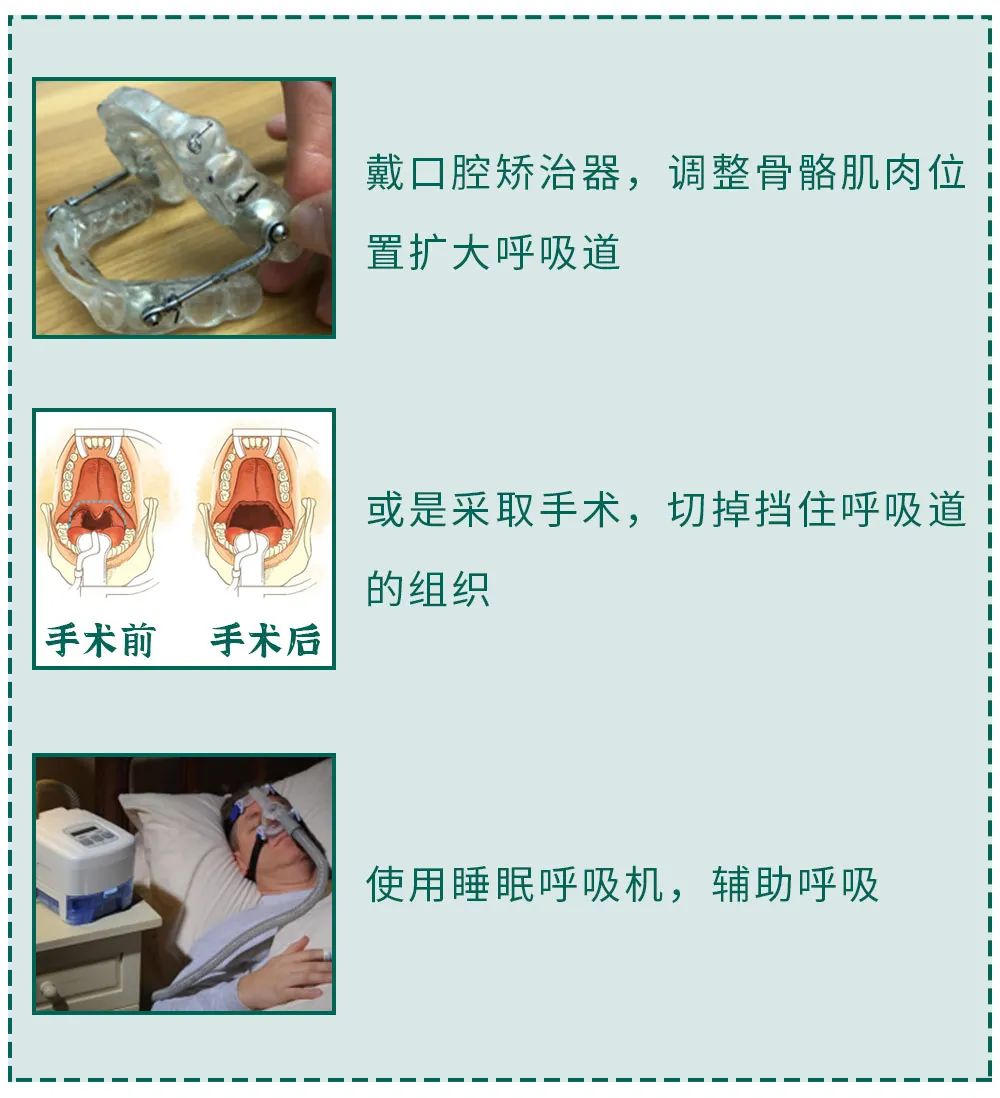

医生可能会根据你的情况,给你几种建议:

总之,“打呼噜”真的是一种病,得治!